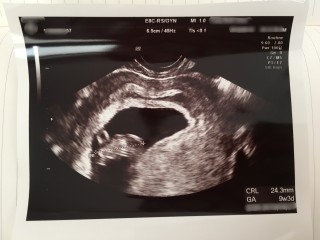

最終生理から計算して、9週0日目に検診に行きましたが、赤ちゃんの大きさは3日分大きく9週3日目の大きさとのことでした! 24.1mm(*^^*) 予定日は、最終生理から計算した日で確定になりました(^-^)誤差が3日なので、修正しないとのことです。 母子手帳ももらって、実感がさらにわきました\(^-^)/ つわりのピークなのか、毎日吐き気とだるさに悩まされますが、安定期目指して乗りきります♪